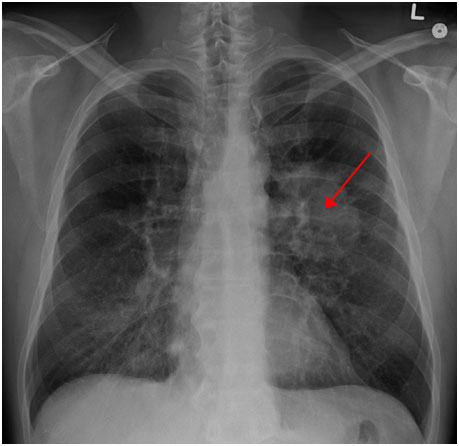

圖示:胸部X光片上顯示的肺癌 來(lái)源:James Heilman, MD/Wikipedia